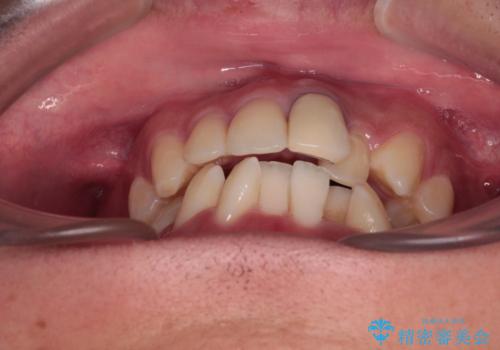

気になる前歯のデコボコと八重歯 ワイヤー矯正ですっきりと

- 前歯のデコボコや八重歯を気にして来院された患者様です。

他院でワイヤー矯正を行うつもりでいらっしゃったそうですが、通院が難しくなったとのことで当院での治療を希望されて来院されました。

上下ともに歯列幅が狭く、その影響でデコボコになっていたため、ワイヤー装置を用いて歯列を側方に拡大しながら、デコボコを解消していくこととしました。